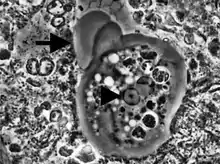

نمونه از دهان بیمار مبتلا به پیوره.

| انتاموبا ژینژیوالیس زیر میکرسکپ | |